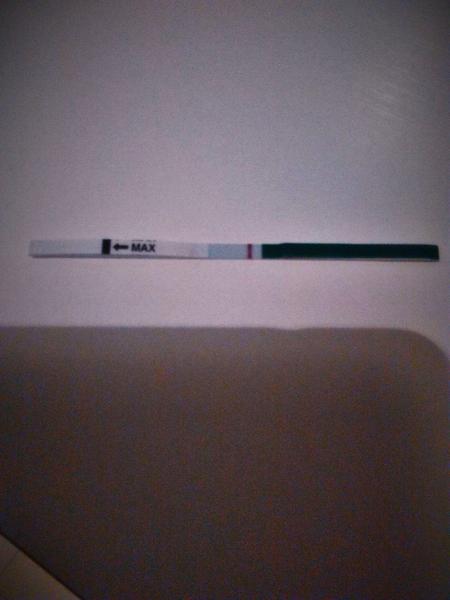

@prskavka2223 Tvoj test z 12.11...Ak maju byt // blizko seba, tak vidim dusika...Pozri trosku som test upravila...Ty si tam nazivo nieco videla? ...Testovala si od tohto testu, ci nie este?

@zuzana92521 na Tvojom vcerajsom teste vidim slabuckeho dusika - neviem, ci aj Ty to na tejto fotke vidis - nalavo od kontrolnej (je to Pepino, ci?)...Neviem, ci je tam naozaj, alebo mam len vidiny - velmi zlu foto si dala, je dost rozmazana, ak mozes, odfot este raz...Jednoznacne testuj za 2-3 dni...Drzim palceky, nech sa Tvoje pocity nemylia a najdes si // - ako po nich tuzis 😉...Hod zas potom foto, ak by si testovala 🙂